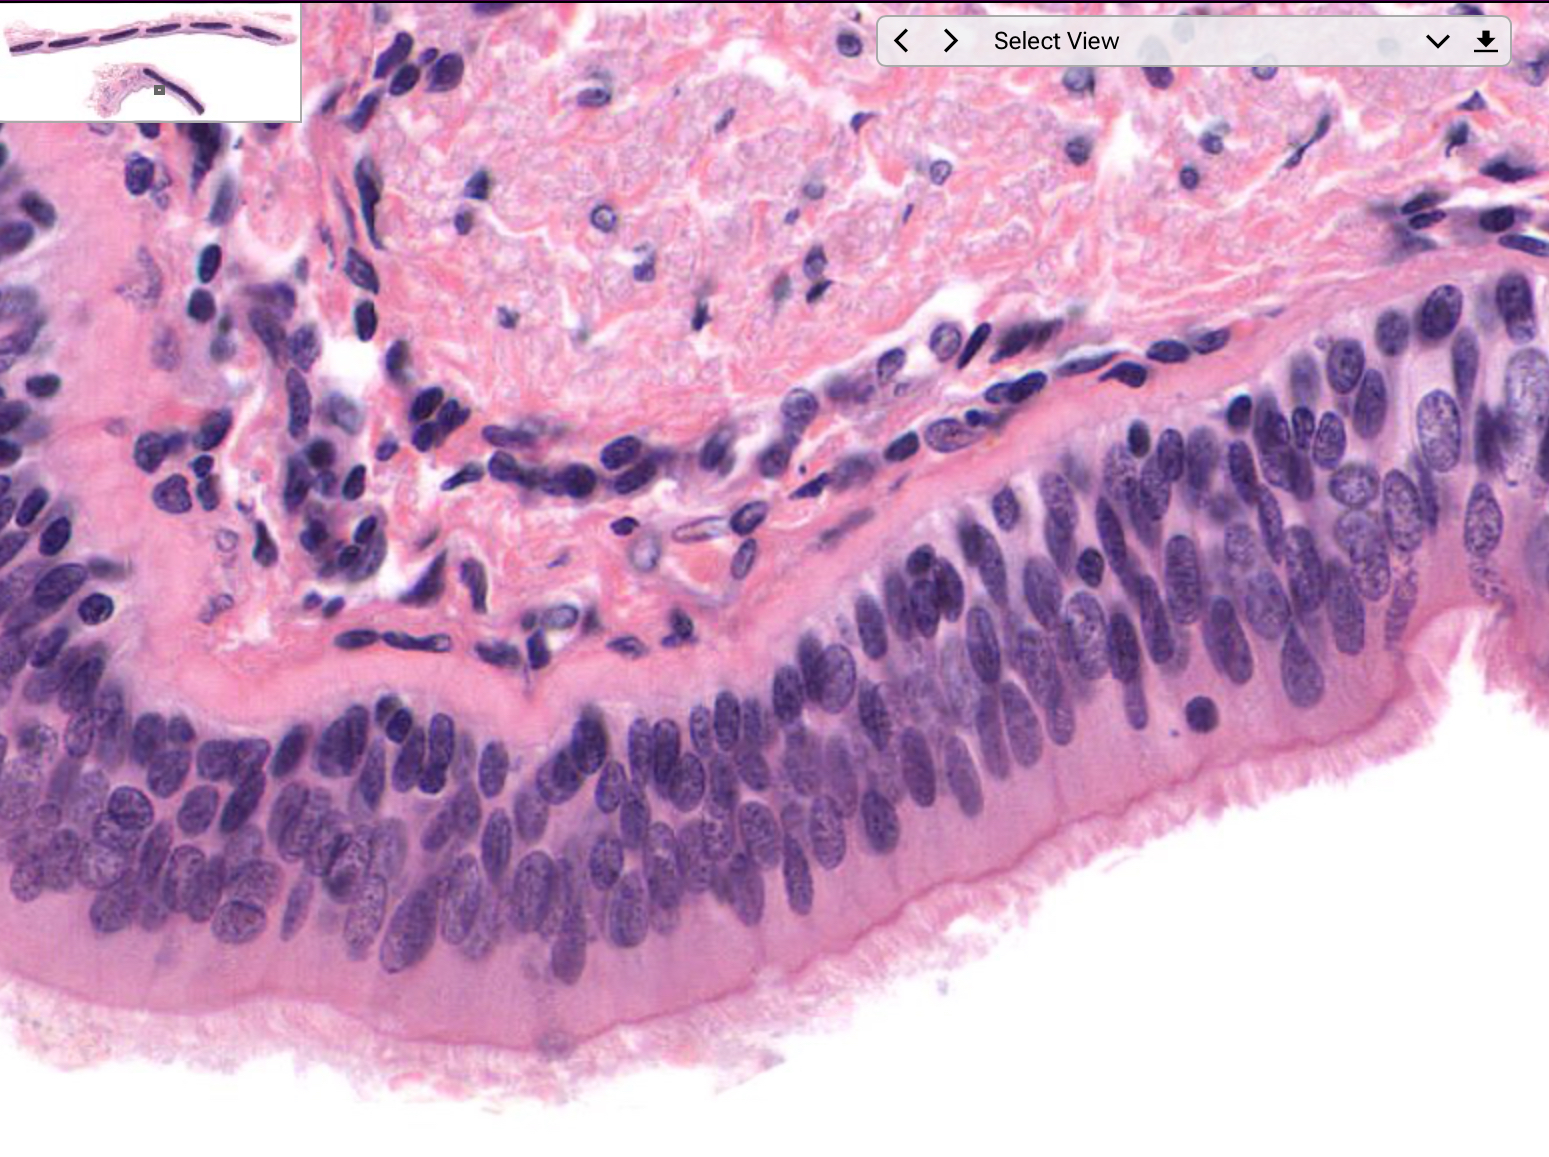

Tissue: pseudostratified columnar epithelium

Location: larynx

Function:

• secretion of mucus

• ciliated: propel mucus by ciliary action